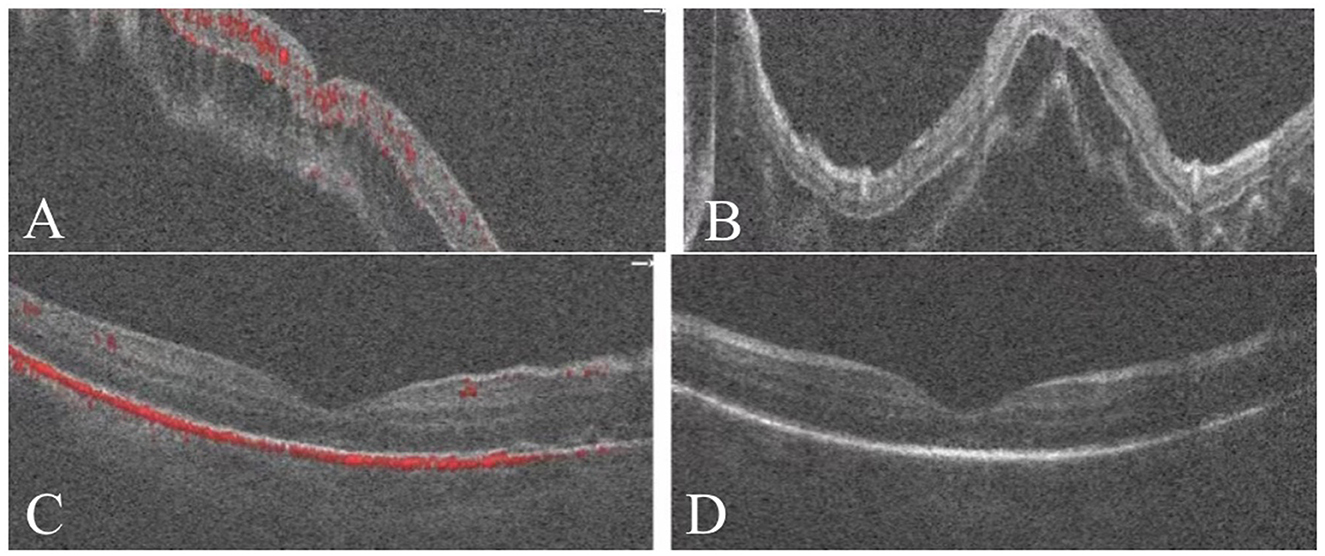

Comparison of fundus photography and OCT findings before and after SB combined with C3F8 surgery is shown in Figures 4, 5.

Figure 5

(A, B) OCT revealed pre-operative separation of the retinal neuroepithelium from the pigment epithelium, with a subretinal fluid-filled area. (C, D) One month post-operatively, retinal reattachment was achieved with absorption of the subretinal fluid and no significant fluid accumulation observed.